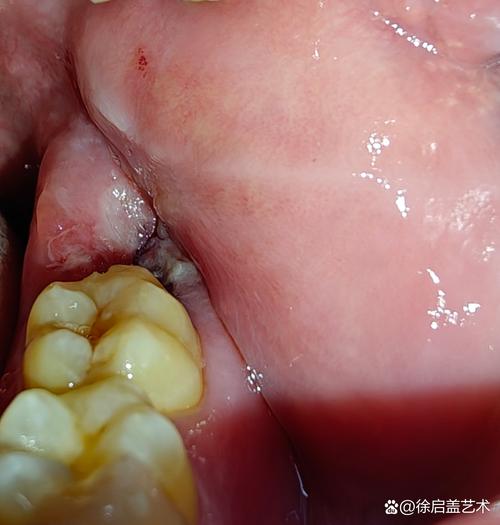

拔完牙食物进牙洞怎么办?

(图片来源网络,侵删)